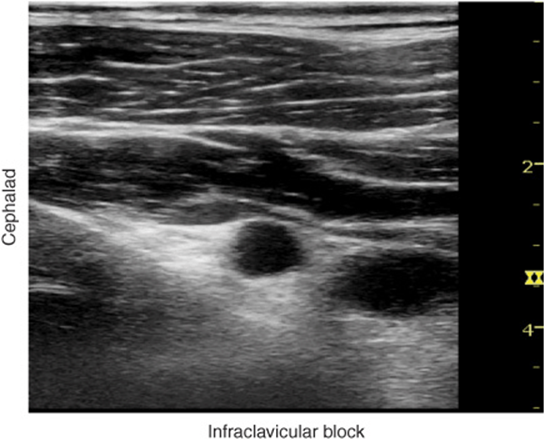

FIGURE 31-3. Unlabeled ultrasound image of the infraclavicular fossa demonstrating pectoralis muscles, their respective sheets, axillary (subclavian) vessels, and the chest wall.